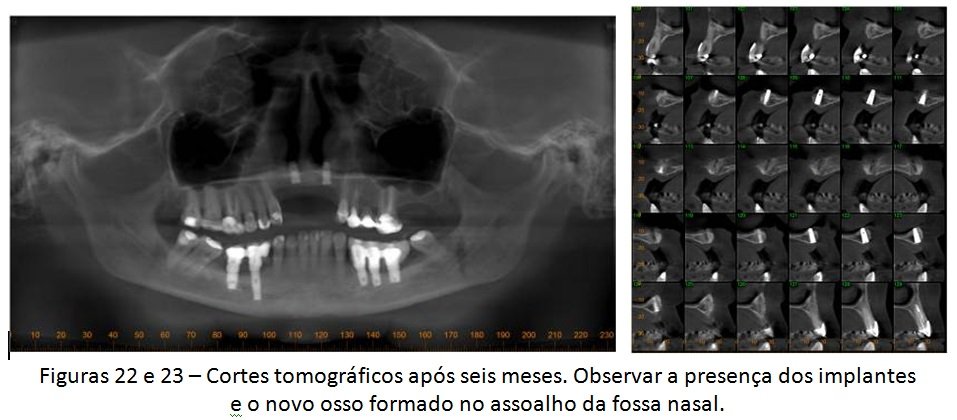

A paciente em questão foi diagnosticada com peri-implantite e recebeu tratamento cirúrgico para eliminação dos sinais e sintomas dessas alterações, mas a doença recorreu e ela acabou perdendo os implantes. A solução escolhida por nós foi o levantamento da cavidade nasal para possibilitar a colocação de dois novos implantes, viabilizando uma futura prótese fixa de quatro elementos. Veja a descrição detalhada do caso abaixo.

O levantamento do assoalho da fossa nasal, apesar de pouco divulgado, pode ser uma interessante solução para casos como esse descrito hoje. Obviamente que poderíamos ter adotado outros tipos de técnicas para se reabilitar a área. Contudo, qualquer outra alternativa teria sido muito mais invasiva, aumentando a morbidade e o tempo de tratamento. Mesmo sabendo que a prótese final será uma reabilitação “dento-gengival”, onde usaremos muita gengiva artificial, acreditamos que essa solução ainda é a melhor escolha em função de todo o histórico do caso e da paciente.